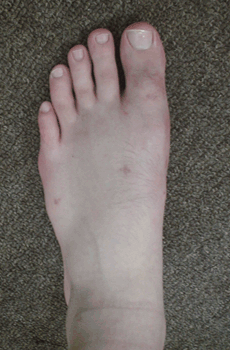

RESULTADOS

Caso 1: Hallux Valgus del adolescente